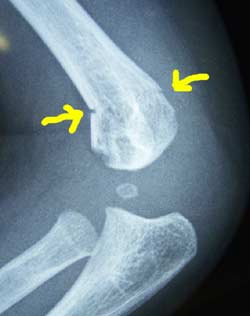

7月28日 まだ段差が確認できる。 しかし骨はまっすぐで、何も異常は認められない。 |